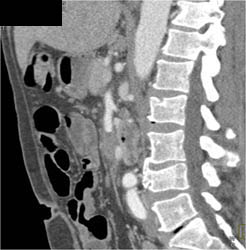

Tumor in Tail of Pancreas Occludes the Splenic Vein